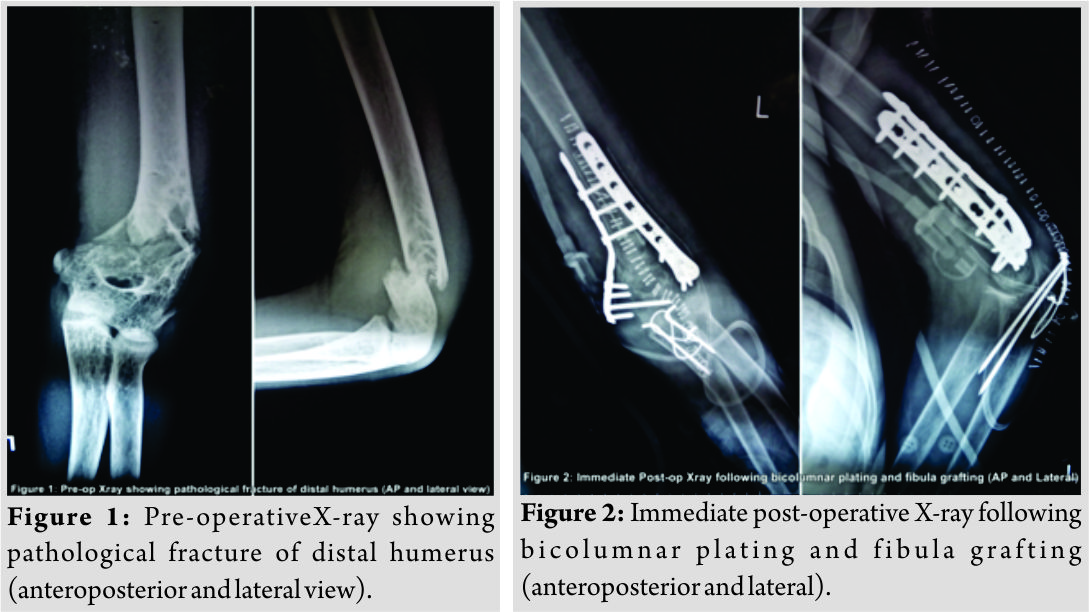

A 16-year-old student was brought to the emergency with a history of trivial fall following which he developed pain and swelling in his left distal arm. X-rays showed a fracture of distal humerus with a lytic lesion involving the distal third of the humerus (Fig.1).Hematological and biochemical investigations were normal. The arm was initially stabilized in a U slab and the patient was taken for fixation in routine OT. Under general anesthesia, the patient was placed in lateral position. Posterior midline incision was taken from distal third of humerus to proximal ulna. Ulnar nerve isolated and olecranon osteotomy was performed to expose the fracture site in distal humerus. A cavity filled with homogenous grayish-white nodular membrane was found. Entire cavity was curetted and the tissue removed was sent for histopathological examination. Fracture margins were freshened. Fibular graft was harvested from the ipsilateral lower limb. The cavity was filled with fibular strut graft. Fixation of the fracture was done with bicolumnar plating (lateral column – posterior and medial column – medial). K-wire tension band wiring was done for olecranon osteotomy (Fig. 2).